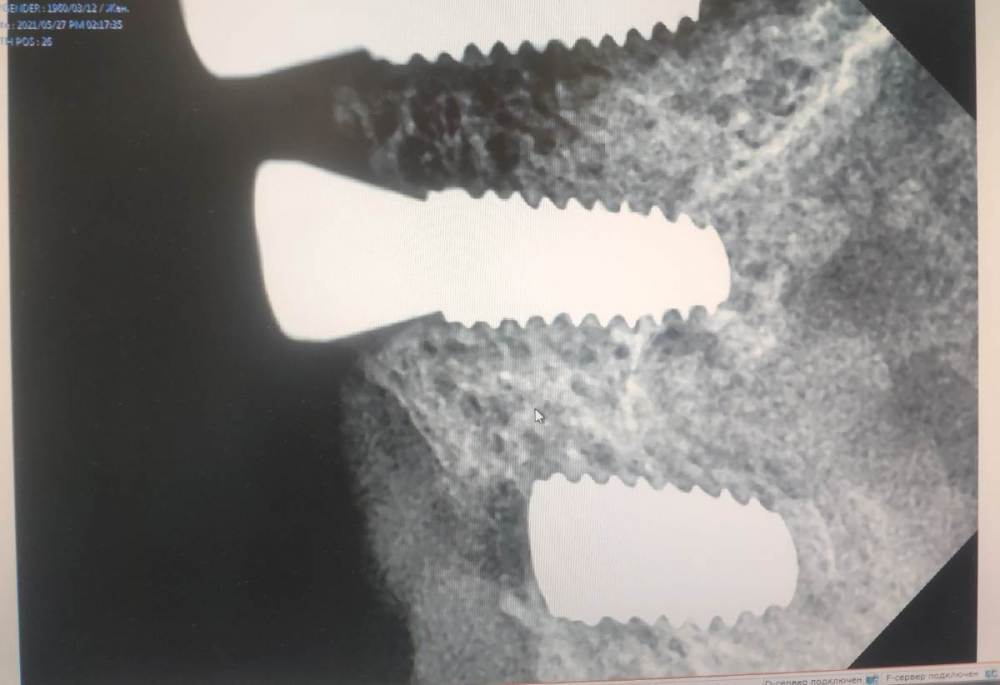

Fin Опубликовано 8 марта, 2023 Поделиться Опубликовано 8 марта, 2023 (изменено) 5 часов назад, Danger сказал: для имплантации хватает 1.5? Мне хватает,вот пример. Это фото монитора, немного обрезанное (обрезал ФИО).У нас датчик vatech 1.5 Изменено 8 марта, 2023 пользователем Fin Ссылка на комментарий